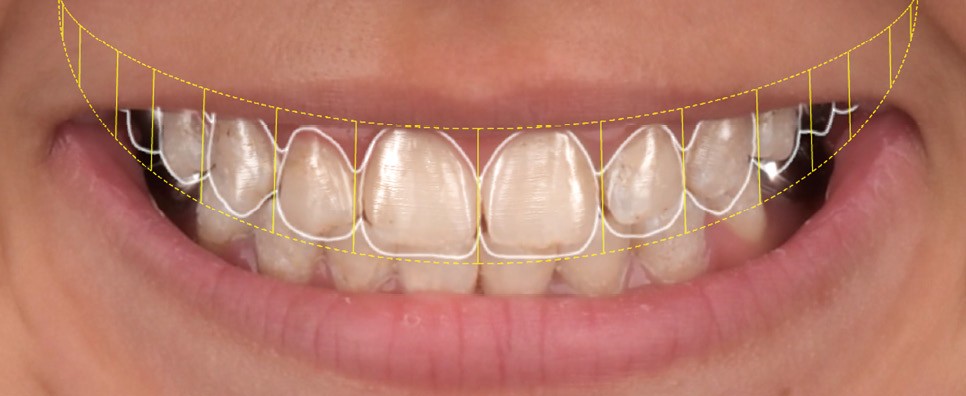

La première étape décisionnelle repose sur une analyse esthétique du visage et du sourire, réalisée à l’aide du logiciel SmileCloud. Cette analyse permet d’évaluer les proportions dentaires, la ligne du sourire et les rapports dento-labiaux. Elle confirme que le traitement vise à la fois la protection d’un émail de mauvaise qualité et l’amélioration de l’esthétique globale, avec notamment une optimisation des proportions dentaires (fig. 5 et 6).